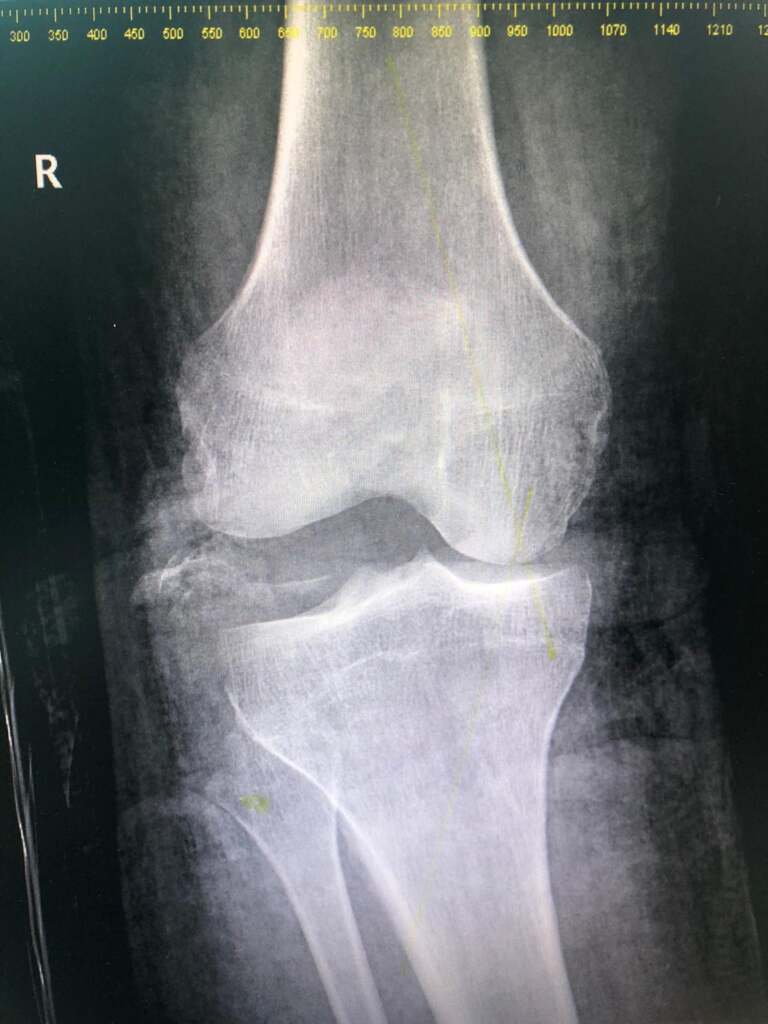

Cu răni pe tot corpul, polițistul care avea atunci 30 de ani a ajuns la Spitalul Județean, unde a fost operat. Medicii au constatat că Octavian Popa avea dublă fractură de femur, fractură de tibie și peroneu, ligamente și meniscul rupte, mușchii gambei smulși și un genunche făcut „praf”. Ca să-i fie vindecate rănile, agentul a primit 120 de zile de îngrijiri medicale, dar, cu recuperare cu tot, a stat în concediu medical 300 de zile.